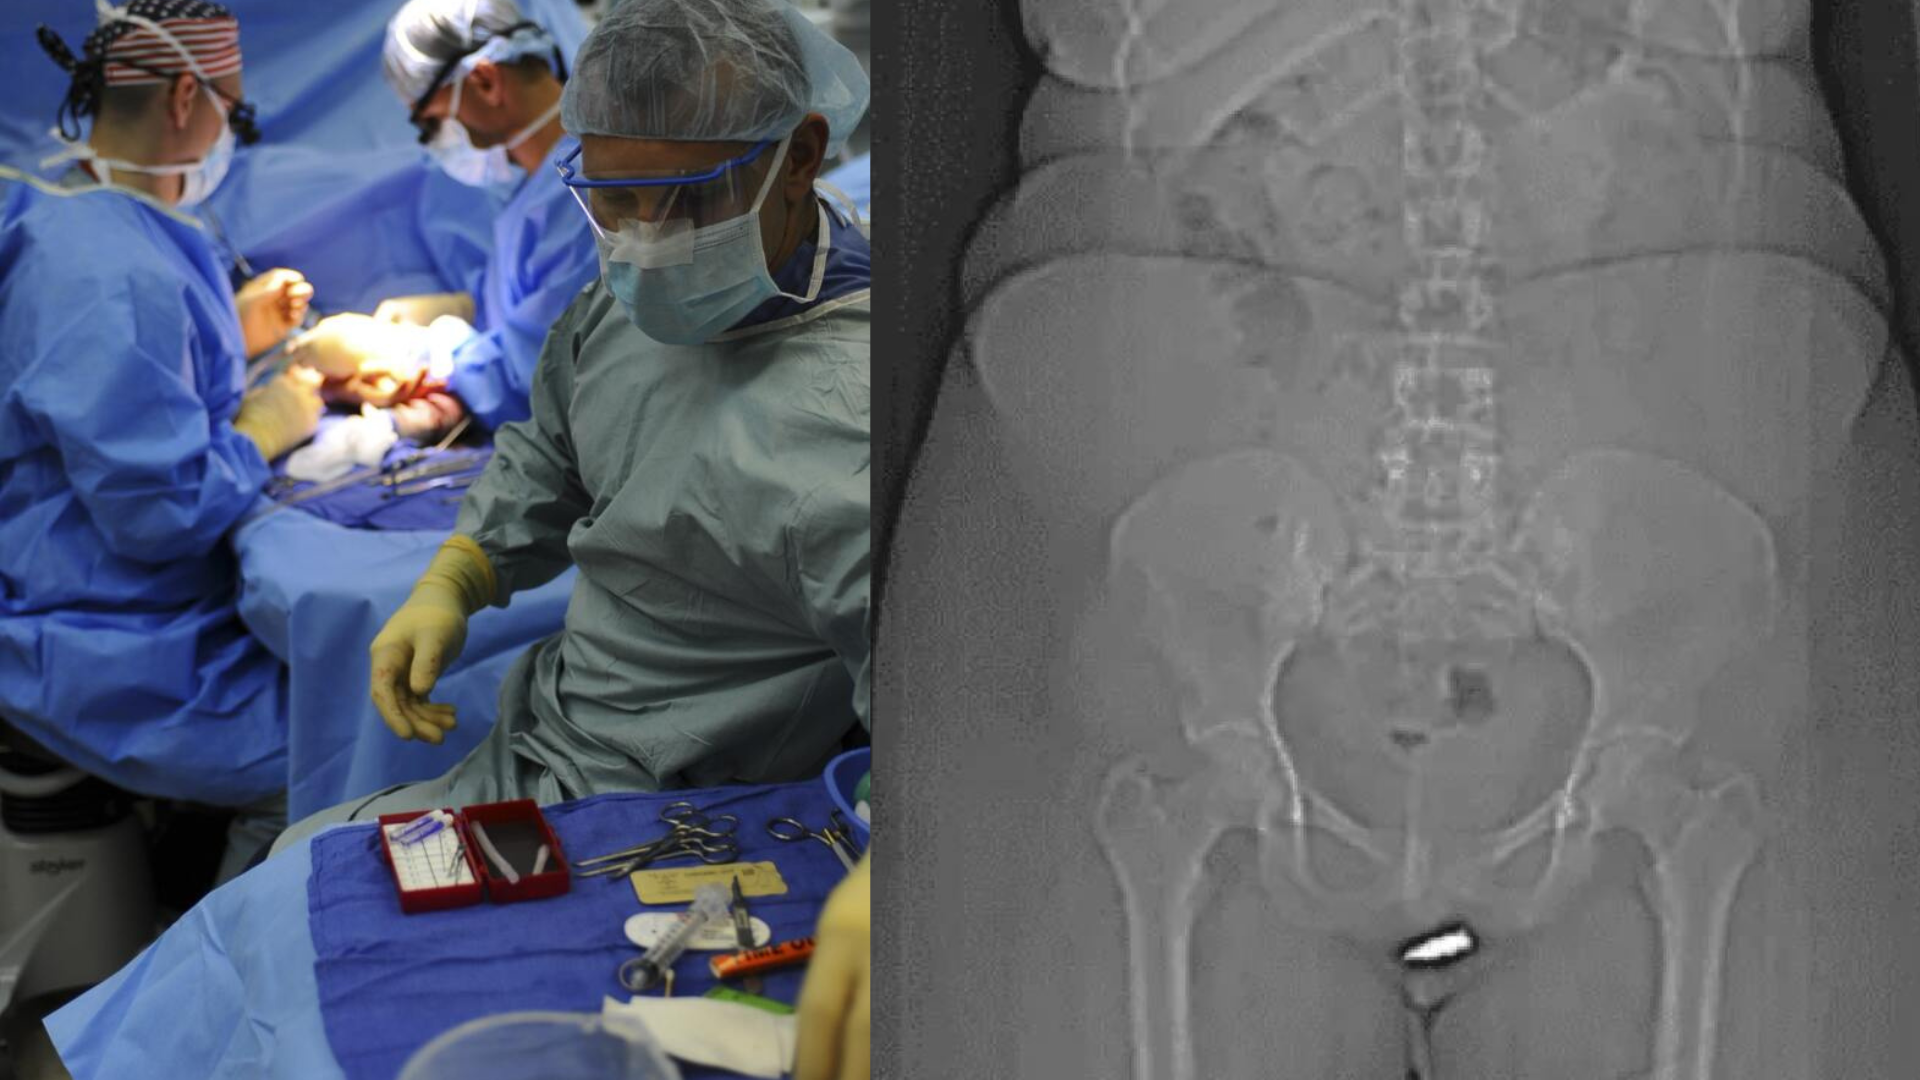

Tras una serie de exámenes, los médicos diagnosticaron que la joven de 24 años tenía «la bala retenida» en su clítoris, por lo cual estaban sorprendidos, ya que es el primer caso conocido.

«Hasta donde sabemos, esta es la primera herida de bala que penetra el área vulvar (la parte externa de los genitales femeninos) con una bala retenida en el clítoris», publicó un estudio publicado en un medio de comunicación.

Después de esto, los médicos realizaron una cirugía con anestesia local y lograron sacarle la bala de la zona afectada, seguido del procedimiento la mujer no sufrió mayor complicación y fue dada de alta al día siguiente.